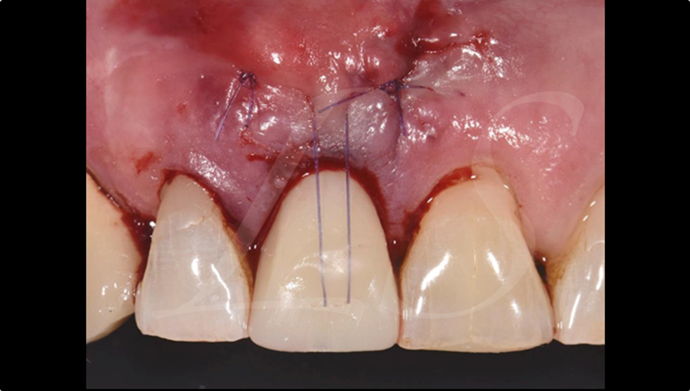

“ONE-DAY implant, one-day smile

”

Clinical case: : R2GATE guided surgery & immediate implant placement

- Courtesy of Dr. Kwang Bum Park, Korea -

Dr. Kwang Bum Park, immediate loading, digital guided surgery, digital ONE-DAY implant, maxillary anterior, #21, guided surgery, immediate loading, AnyRidge, R2GATE, Mega ISQ, MEG Torq, R2GATE Full Surgical Kit

implant system, R2GATE Guide, R2GATE full surgical kit, Mega ISQ